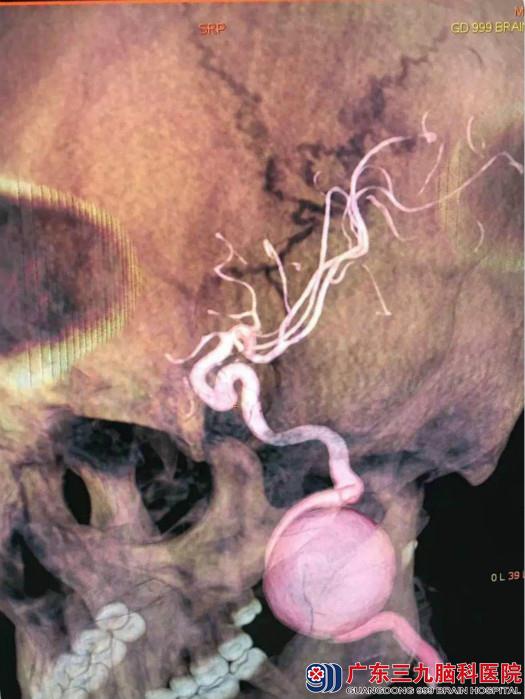

行头颅CTA检查提示:左侧颈内动脉C1段示一巨大动脉瘤,大小约为28.3mm×32.8mm。进一步行全脑血管造影示:左侧颈内动脉颈段巨大动脉瘤,囊状、窄颈,大小约23mm*25mm,瘤体朝前生长;行左侧颈内动脉颈段动脉瘤球囊闭塞试验,术中体感诱发电监测,造影证实左侧颈内动脉起始部完全闭塞约30分钟;闭塞过程中不同时段监测波形、与患者交流等观察病情变化,证实前交通、后交通均开放代偿左侧半球。

术后复查CTA